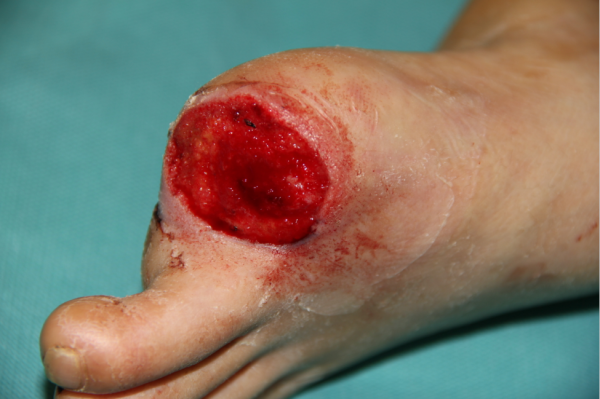

玉米机伤右足复合组织缺损,腓骨皮瓣修复,术后12天,伤口愈合良好,今日出院清创后

术中

跖趾关节成形